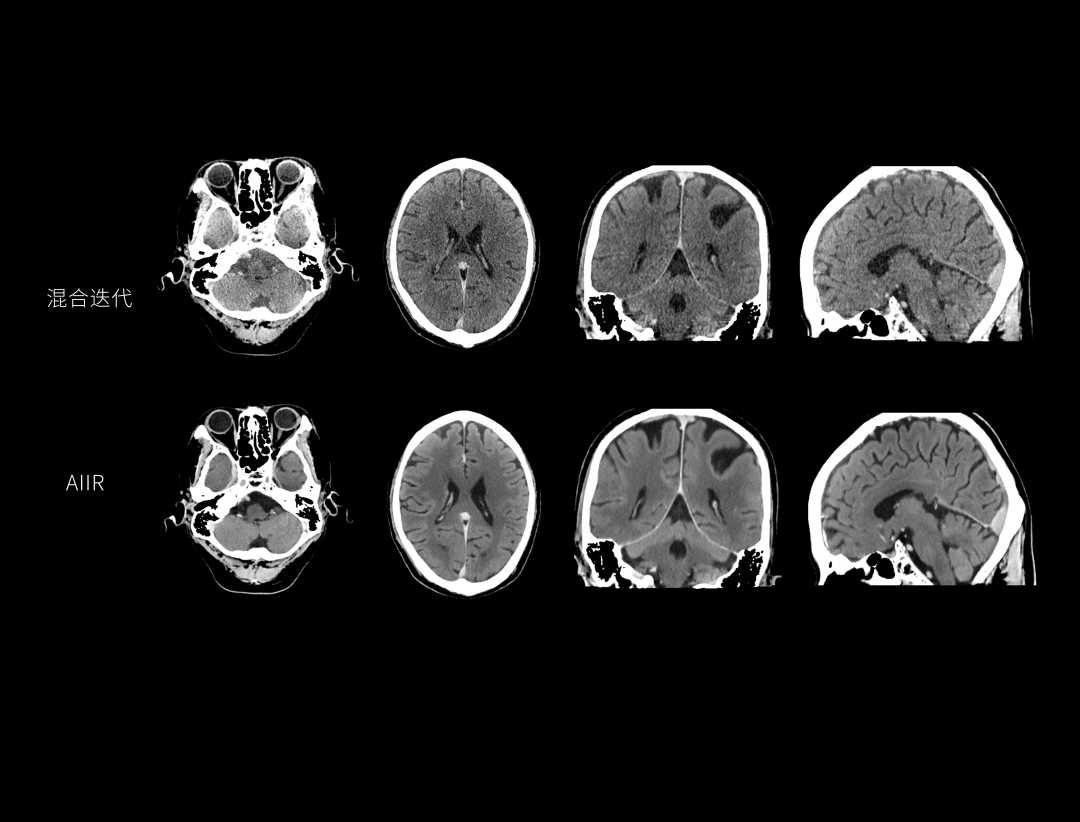

AIIR图像重建提升结果图像可解释性与算法鲁棒性,获得低剂量下的高清成像,超越传统,引领CT成像新标准